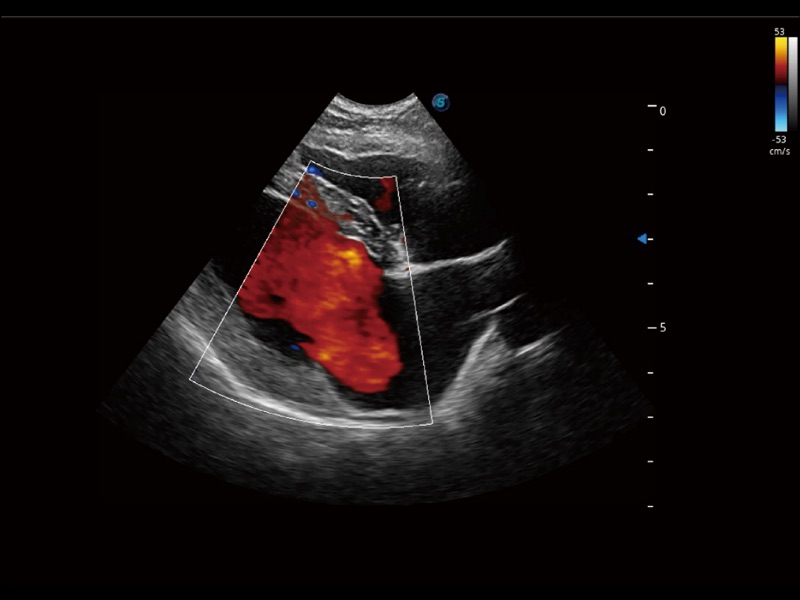

(犬)髂动脉血流